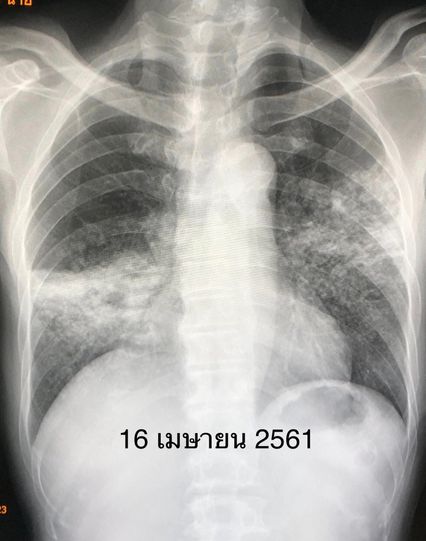

“ผลตรวจร่างกาย ฟังเสียงปอดพบความผิดปกติ เมื่อเอกซเรย์ปอดมีฝ้าขาวทั้งสองข้าง แพทย์จึงสั่งเก็บเสมหะส่งย้อมเชื้อพบวัณโรค 1+ ตรวจรหัสพันธุกรรมพบเชื้อวัณโรคไม่ดื้อยาริแฟมพิซิน เพาะเชื้อขึ้นวัณโรคไวต่อยาไอโซไนอะซิด ริแฟมพิซิน และอีแธมบูทอล สรุปว่า ผู้ป่วยเป็นวัณโรคปอดชนิดไม่ดื้อยา ได้เริ่มยาไอโซไนอะซิด ริแฟมพิซิน พัยราซินาไมด์ และอีแธมบูทอล หลังกินยาวัณโรค 2 สัปดาห์ ผู้ป่วยคลื่นไส้ อาเจียน เบื่ออาหาร ค่าเอนไชม์ตับขึ้นสูง SGOT 312, SGPT 199 แพทย์สงสัยว่าแพ้ยาริแฟมพิซินทำให้ตับอักเสบ จึงหยุดยาริแฟมพิซิน ให้ยามอกซิฟลอกซาซิน (Moxifloxacin) แทนยาริแฟมพิซิน ค่าเอนไชม์ตับลดลง SGOT 57, SGPT 36” หมอมนูญระบุ

เคสนี้แพทย์รักษาด้วยการให้กินยาวัณโรคไอโซไนอะซิด พัยราซินาไมด์ อีแธมบูทอล และมอกซิฟลอกซาซิน ต่อเนื่อง 1 ปี ไม่ไอ มีความอยากอาหาร น้ำหนักขึ้น 14 กิโลกรัม ผลเอกซเรย์ปอดดีขึ้นมาก หลังหยุดกินยา 4 ปี วัณโรคไม่กลับมาใหม่ เอกซเรย์ปอดยังมีร่องรอยวัณโรคเก่าบ้าง